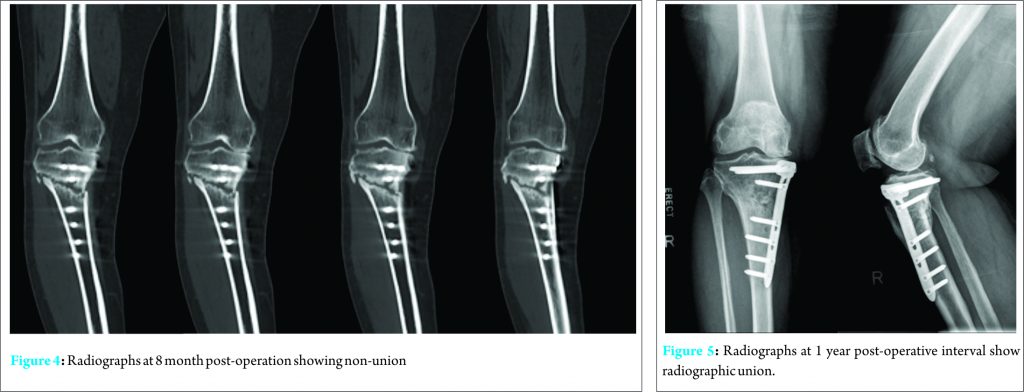

However, she continued to experience pain over the osteotomy site up till 6 months post-operatively. Pain was exacerbated on standing and ambulation. Repeat radiographs showed minimal callus formation over previous osteotomy site (Fig. 3). She was treated conservatively with continued protected weight bearing. However, her symptoms deteriorated and she developed a fix flexion deformity of her right knee. A computed tomogram performed 8 month post-operatively revealed non-union of the osteotomy site with hardware failure and loss of correction (Fig. 4). Three proximal screws were broken and 1 screw had back-out. The proximal tibia was angulated laterally in varus and anteriorly increasing the tibial plateau slope. Inflammatory markers were not elevated.

The patient subsequently underwent revision plating with autologous bone graft. The surgical approach was similar to the index surgery. Intra-operatively, findings were consistent with CT scan results. The screws were completely removed together with the Tomofix plate. Bone edges were freshened and the alignment was corrected under radiographic imaging guidance. Autologous cancellous iliac crest bone grafts were harvested and compacted into the osteotomy site. A proximal tibial locking plate was placed on the posteromedial aspect and locking screws were used to secure the fixation. The previous plate was medial. Intraoperative cultures sent were negative for infection. Post-operatively, the patient progressed from non-weight bearing to partial weight bearing at 3 months and full weight-bearing at 6 months post-operatively. She no longer experienced pain at the osteotomy site and repeat radiographs performed at 1 year post-operatively showed union (Fig. 5). She was able to ambulate without any walking aids and no longer has any limitations in her daily activities.